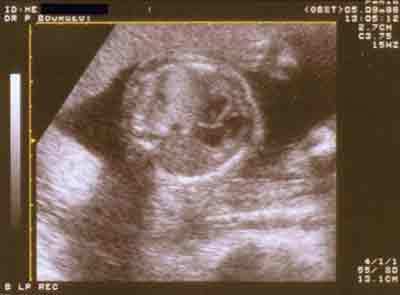

Diagnostic différentiel (Hernie postéro latérale gauche) : séquestration pulmonaire